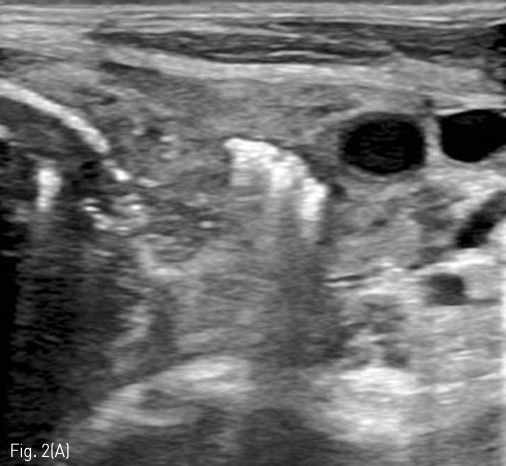

Fig 2A

(A) On US, inflated balloon with a mixture of normal saline and contrast medium (long arrow) is seen echogenic in the esophagus between Lt. common carotid artery (dotted arrow) and Lt. thyroid gland. (short arrow)

Fig 2B

(B) On fluroscopy, the position of inflated balloon is adjusted between the thoracic inlet and Lt. clavicle. Under US guidance, the Balloon is punctured with an 18 G puncture needle through the left neck.